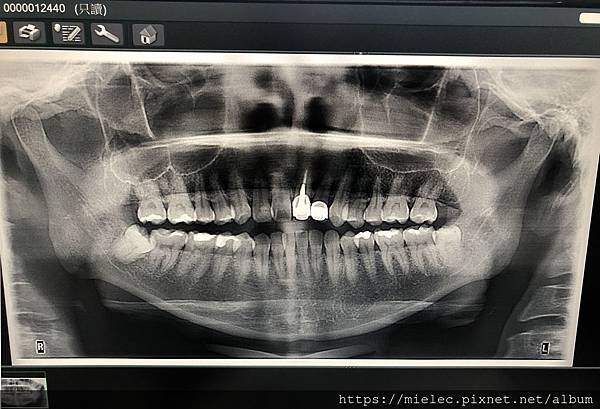

一是困擾多年的二顆長歪智齒順利拔除,這二顆長歪的智齒由於很靠近神經,醫生說明有傷到神經的可能,所以原本打算跟它們和平共處,但今年3月起時不時智齒痛,當時疫情使得人心惶惶,於是延至6月分二次拔除左右二顆下方的阻生齒,臉一度腫成花栗鼠(好啦!沒那麼可愛),也發燒到38度,不過最後沒傷到神經的順利拔除二顆智齒

PS: 小編於網路多人推薦的"宏陽牙醫診所"就診,由"周豐智"醫師操刀,很推薦喔! 自費二組共6000元的膠原蛋白,小編的保險公司有給付